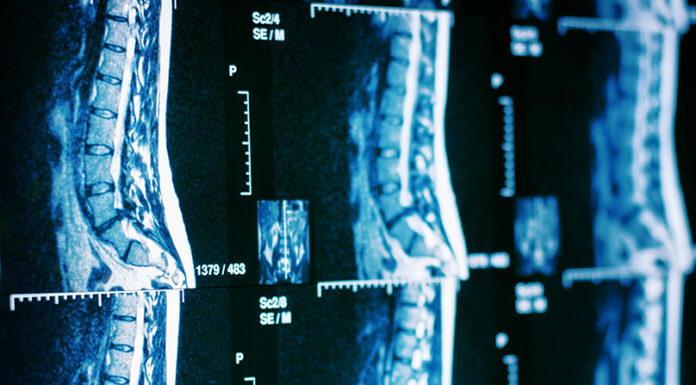

Ρομποτική χειρουργική σπονδυλικής στήλης: Τα πλεονεκτήματα

Η χειρουργική της σπονδυλικής στήλης με τη βοήθεια της ρομποτικής πλοήγησης είναι μια πολλά υποσχόμενη τεχνολογία, η εφαρμογή της οποίας διευρύνεται συνεχώς, με το Θεραπευτήριο Metropolitan να αποτελεί το πλέον συστηματικό πεδίο εφαρμογής της στην Ελλάδα, καθώς μια κορυφαία ομάδα, που έχει παρακολουθήσει στις...